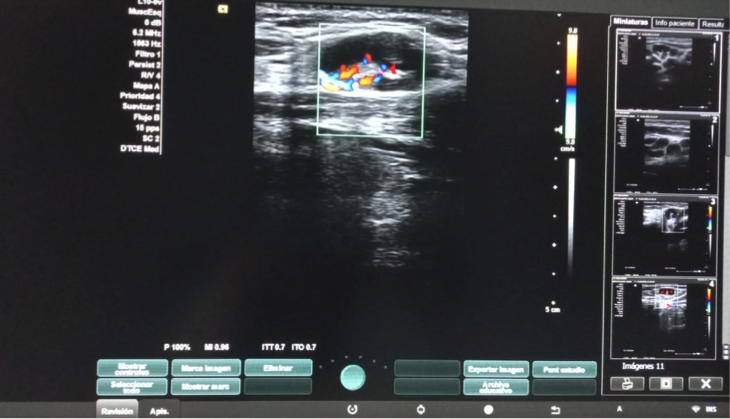

Hallazgos ecográficos

Dos adenopatías en territorio laterocervical derecho, con hilio central y doppler positivo, alguna con diámetro transversal superior al longitudinal, de probable origen reactivo y una adenopatía supraclavicular sin hilio central y con vascularización generalizada.

El diagnóstico histopatológico confirmó una linfadenitis histiocítica necrotizante, compatible con EKF, entidad benigna, poco frecuente, autolimitada y con clínica variable, pudiendo simular a patología infecciosa, trastornos linfoproliferativos y determinadas patologías reumatológicas. La clinica es en forma de adenopatías cervicales, fiebre, sudoración nocturna y mialgias. El diagnóstico es histopatológico, pero la ecografía realizada en Atención Primaria fue esencial para orientarlo, puesto que mostraba evidentes criterios de benignidad acompañados de otros hallazgos (ganglios mayores de 10 mm algunos con mas diámetro transversal que longitudinal y la presencia de una adenopatía supraclavicular) que precisaban descarte y diagnóstico diferencial de otras entidades.